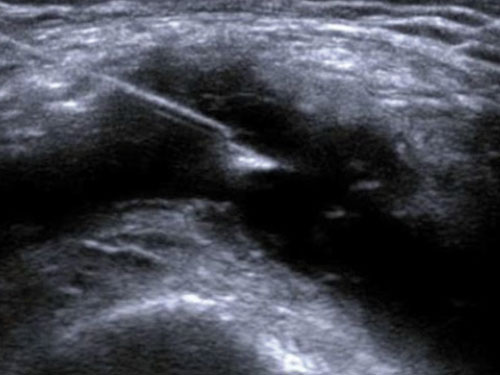

microV: Hemodynamické hodnocení s vysokou citlivostí a vysokým prostorovým rozlišením pro charakterizaci vaskularizace lézí ve všech klinických aplikacích, rychlé a neinvazivní.